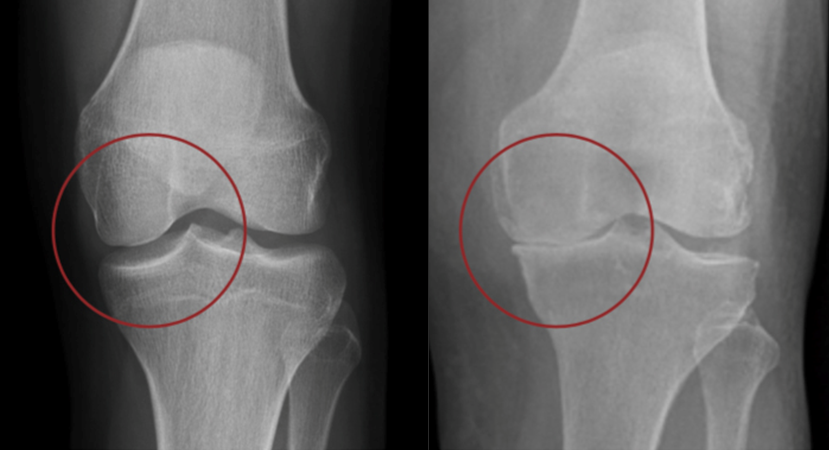

Dans le genou, les os sont recouverts d’un cartilage, une sorte de revêtement très lisse, qui leur permet de glisser l’un sur l’autre sans frottement quand on marche et qu’on bouge le genou. L’arthrose, c’est quand ce cartilage s’use, se raye ou se fissure, parfois jusqu’à l’os. Si la surface n’est plus lisse, les mouvements du genou « accrochent » et on peut avoir mal en marchant, des difficultés à bouger le genou, et le genou qui gonfle : il produit du liquide pour essayer de « huiler » l’articulation.

L’arthrose peut toucher une partie du genou (compartiment interne, externe, ou antérieur) ou plusieurs.